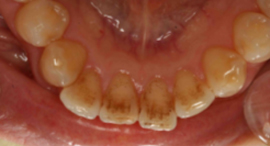

PMTC・歯のクリーニング前